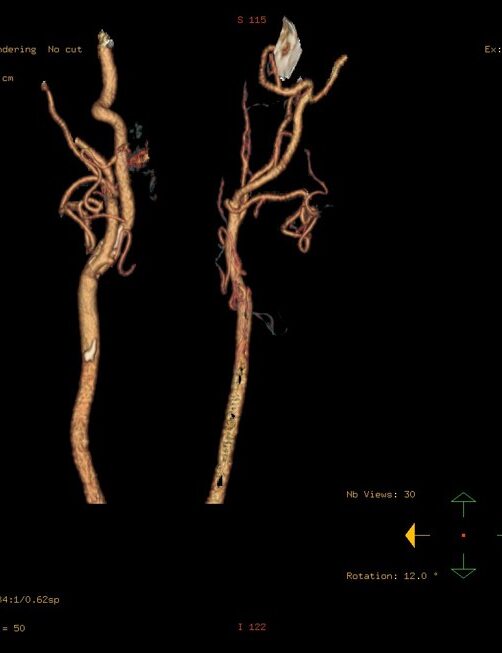

Computed tomography angiography (CTA) combines a CT scan with a special dye or contrast material to produce pictures of blood vessels and tissues in a section of your body.

CT angiography uses a CT scanner to produce detailed images of blood vessels and tissues throughout the body. An iodine-rich contrast material (dye) is usually injected through a small catheter placed in a vein of the arm. A CT scan is then performed while the contrast flows through the blood vessels to the various organs of the body. After scanning, the images will be processed using specialized software and a computer, and reviewed in different planes and projections.